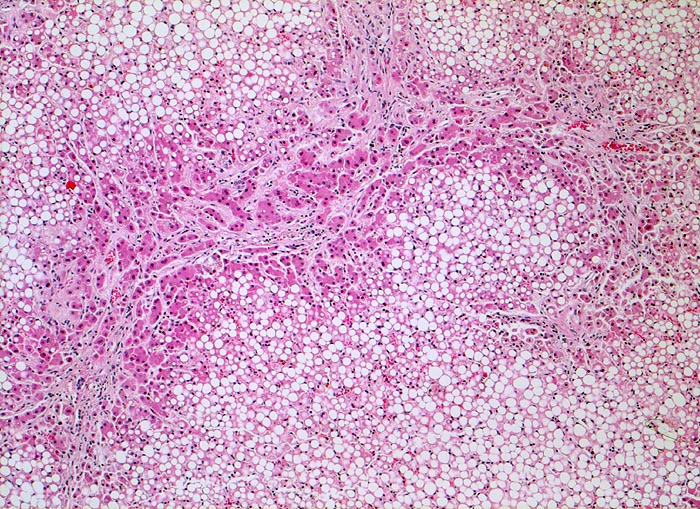

unvollständiger zirrhotischer Umbau, Steatose

Bindgewebebige Septen durchziehen das grobtropfig verfettete Parenchym und bilden einen unvollständigen Knoten.

Für die Diagnose einer Leberzirrhose wird ein diffuser knotiger Umbau der gesamten Leber gefordert. Die Grenzen zwischen unvollständigem und vollständigem zirrhotischem Umbau sind fliessend.